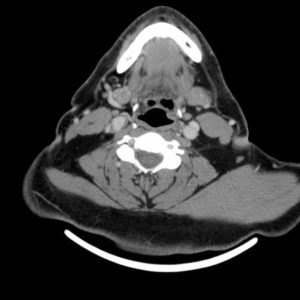

K hạ họng

Lượt xem: 241» 24-03-2019 -

K hạ họng

Lượt xem: 304» 24-03-2019 -

K hạ họng

Lượt xem: 198» 24-03-2019 -